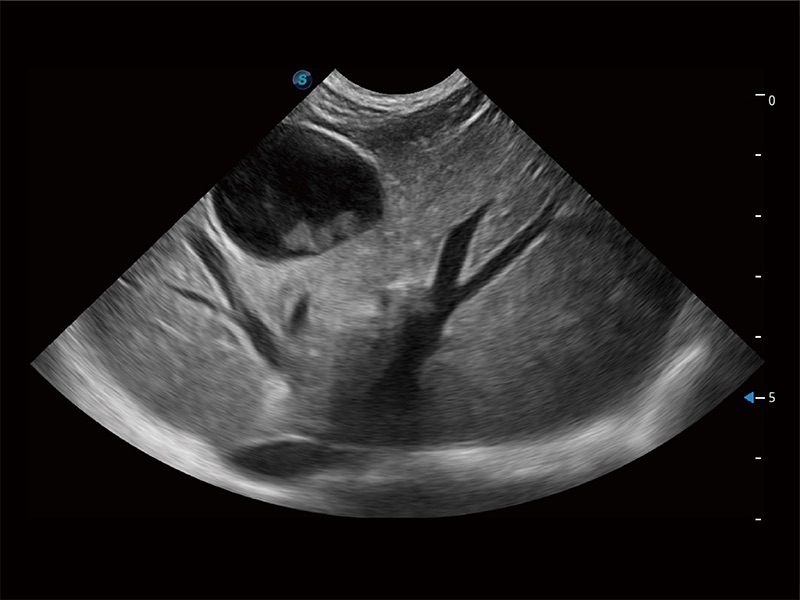

高性能和先進(jìn)的臨床應(yīng)用工具可以為動(dòng)物醫(yī)生提供臨床信心。ProPet 80 搭載了先進(jìn)的腹部和淺表應(yīng)用工具,幫助醫(yī)生在日常臨床實(shí)踐中發(fā)揮前所未有的作用。

ProPet 80 專為動(dòng)物醫(yī)生設(shè)計(jì),對(duì)不同的動(dòng)物體型和生理結(jié)構(gòu)作出了針對(duì)性的優(yōu)化。通過動(dòng)物影像專用軟件,可滿足個(gè)性化的應(yīng)用需求,幫助動(dòng)物醫(yī)生獲得更精確的診斷數(shù)據(jù)。

ProPet 80 全新的動(dòng)物超聲智能軟件和豐富的探頭群,為動(dòng)物醫(yī)生提供了高清晰度和精細(xì)分辨率的圖像,無論在寵物、馬科、畜牧還是實(shí)驗(yàn)室動(dòng)物等應(yīng)用中都可以輕松應(yīng)對(duì),為您的日常工作帶來滿意的體驗(yàn)。